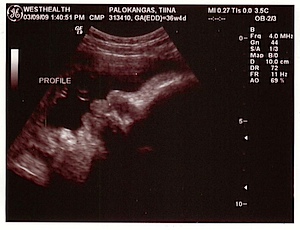

Digi-Masa

Me oltiin tänään ultrassa. Kätilö ei voinut olla tunnustelemalla varma, onko vauva pää vai pylly alaspäin (ja äiti tuntee hötkyilyä niin ylhäällä kuin alhaallakin), niin laittoivat meidät ultraan. Ultrassa olikin aika mukavaa! Vauva on tosi […]